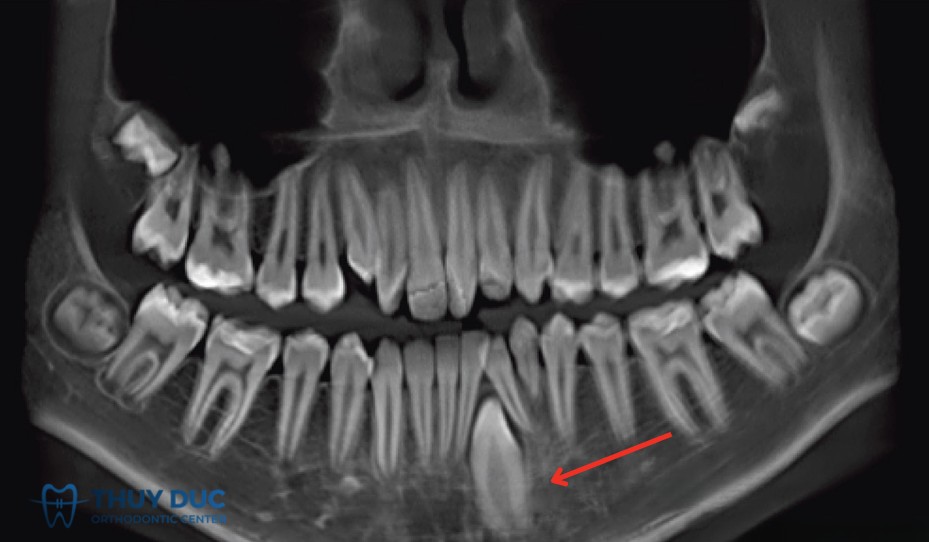

Vì vậy, phương pháp chẩn đoán chính xác nhất là chụp X-quang (thường là phim panorama hoặc phim cận chóp). Trên thực tế, rất nhiều bệnh nhân chỉ phát hiện mình có răng mọc ngầm khi đi khám và chụp phim để điều trị một vấn đề khác, ví dụ sâu răng, viêm nha chu hoặc chuẩn bị niềng răng.

2.3 Răng cửa mọc ngầm

Răng cửa mọc ngầm ít gặp hơn nhưng ảnh hưởng trực tiếp đến thẩm mỹ và phát âm. Nguyên nhân thường do răng sữa rụng muộn hoặc có vật cản trong xương hàm như răng thừa. Điều trị sớm giúp bảo tồn răng và hạn chế lệch khớp cắn.